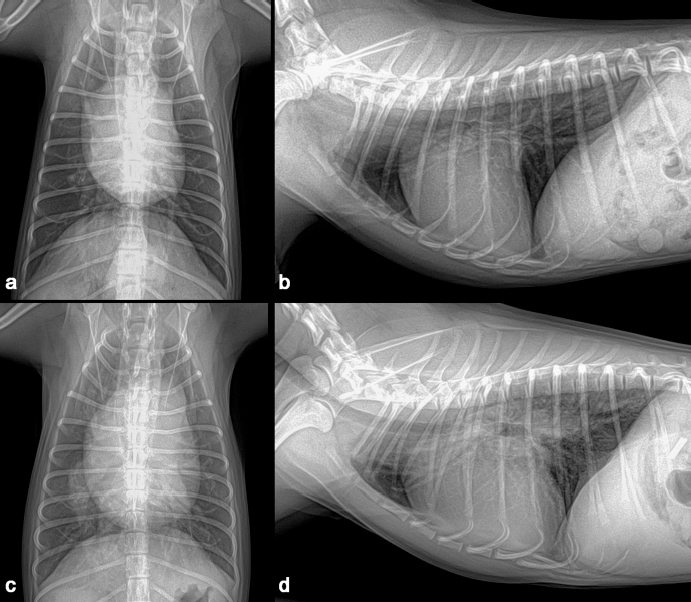

A 1-year-old neutered male Maltese dog weighing 1.4 kg was referred to the Veterinary Teaching Hospital showing microhepatica (Fig. 1a) and hyperammonemia. The dog did not show clinical signs related to portosystemic shunt previously. Although its postprandial ammonia level was in the reference range [18 μmol/l, reference interval (RI): 0–98 μmol/l], hypoalbuminemia (2.1 g/dl, RI: 2.6–3.3 g/dl) and increased levels of serum bile acid (177 μmol/l, RI: 0–25 μmol/l), alanine transaminase (ALT) (254 IU/l, RI: 21–102 IU/l), and alkaline phosphatase (ALP) (1347 IU/l, RI: 29–97 IU/l) were identified. No abnormalities, including cardiac murmur, were observed during physical examination. For a more thorough examination, computed tomography was used, and a CPSS (porto-caval shunt) was diagnosed (Fig. 2a and b). After preoperative medical stabilization, surgery was performed for shunt attenuation. Anesthesia was induced with propofol (8 mg/kg, IV) and maintained by isoflurane. Perioperative pain was managed by tramadol (5 mg/kg, IV). From the xiphoid process to the pubis, a standard ventral midline approach was taken. After dissecting the shunt from surrounding tissues, portal pressure was measured from the jejunal vein. Baseline portal pressure was measured to be approximately 7–8 mmHg (RI: 6–10 mmHg). It increased to 13–14 mmHg after temporary complete occlusion of the shunt. The shunt was attenuated using a cellophane band. The abdominal cavity was closed in a routine manner. Its recovery from anesthesia was uneventful. Postprandial serum bile acid (12 μmol/l), albumin (2.6 g/dl), and ALT (29 IU/l) levels returned to their normal ranges at 1 month after the operation. Its serum ALP level also decreased to 430 IU/l, although it was above the RI. An increase in liver size was observed by abdominal radiographs 1 month after surgery (Fig. 1b). Because the majority of the CPSS anomalies were cured throughout the follow-up period, the dog was able to return to normal life without the need for supporting medicine. One year after surgery, the dog was presented to the Veterinary Teaching Hospital for exercise intolerance. Blood gas analysis revealed hypoxemia (73.6%, RI: 95%–99%). A cardiac murmur was auscultated. When compared with thoracic radiographs evaluated at the time of the operation (Fig. 3a and b), the vertebral heart scale increased from 10 to 11.7, indicating generalized cardiomegaly (Fig. 3c and d). Following echocardiography revealed ASD and pulmonary hypertension (Fig. 4a and b). A bubble study confirmed right-to-left shunt. Surgical or interventional therapy was not contemplated due to the dog's tiny size (1.7 kg) and reversed interatrial shunt. Thus, medical treatment was performed to reduce pulmonary hypertension (sildenafil, 1.5 mg/kg, PO, q12 hours). Hypoxemia was improved (94%) after a month of treatment. The dog's activity intolerance had been overcome, according to the owner. As a response to the medical treatment was generally good, therapy was still maintained without changing medication for the next 16 months after diagnosis of the ASD.

Fig. 4. Echocardiography (right parasternal long-axis four-chamber view) showed an atrial septal defect (a) and color Doppler revealed a right-to-left shunt (b).

The present study described a dog with two types of vascular anomalies. Similar to a previous study (Greenhalgh et al., 2010), the dog showed a good prognosis after surgical attenuation of the CPSS. Cardiomegaly was not seen on preoperative thoracic radiographs, despite the fact that ASD was suspected at the time of CPSS diagnosis. ASD is generally a well-compensated disease (Chetboul et al., 2006) and the dog may show no clinical symptoms over 2 years. When it was presented 1 year after the operation, the chief complaint was exercise intolerance of the dog. Compared with the previous clinical data on the dog, it could be suspected that ASD caused pulmonary hypertension, which might have resulted in a right-to-left shunt (Guglielmini et al., 2002). This hemodynamic physiology is generally defined as Eisenmenger’s syndrome, which can cause cyanosis and exercise intolerance (Berger et al., 2010). In veterinary medicine, surgical treatment for ASD is challenging for small-sized dogs (Pelosi et al., 2013). Although a case of ASD closure in a toy poodle was recently published (Sugimoto et al., 2020), owing to the dog's pulmonary hypertension and reversed interatrial shunt, surgical and interventional therapy for the dog was not explored in the current investigation. Surgical treatment for Eisenmenger’s syndrome, such as heart-lung transplantation, has been performed in human medicine. However, its morbidity and mortality remain high (Waddell et al., 2002). As an alternative to surgical treatment, medical management by sildenafil can be effectively applied to patients with this condition (Garg et al., 2011). The dog in the present study also responded well to sildenafil, and its clinical symptoms were resolved. In previous human medicine studies, about 9% to 30% of patients have CPSS concurrent with ASD (Franchi-Abella et al., 2010; Kim et al., 2012). Like human medicine, this study reports a rare case of CPSS concurrent with ASD in a dog. Because congenital heart illnesses are easily recognized by echocardiography, it is also suggested for dogs with CPSS to get an echocardiogram for early detection of additional cardiovascular defects, even if there are no symptoms.